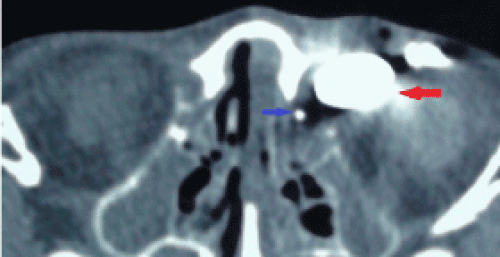

| Figure 1D: Axial computed tomography: Injection of contrast material from orificium fistula and normal lacrimal puncta (first patient). Red arrow: lacrimal diverticulum filled with contrast material; Blue arrow: normal lacrimal sac filled with contrast material. |